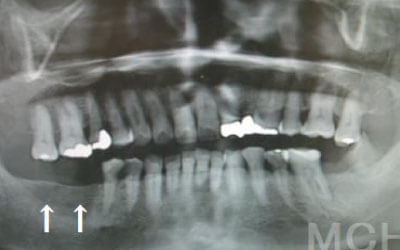

1)ブリッジ

2)歯を大きく削る+支えの歯に1.5倍の力がかかる

3)前後の歯の寿命が著しく減る

ブリッジの支えの歯は、データでは10年以内に68%が抜歯になります。